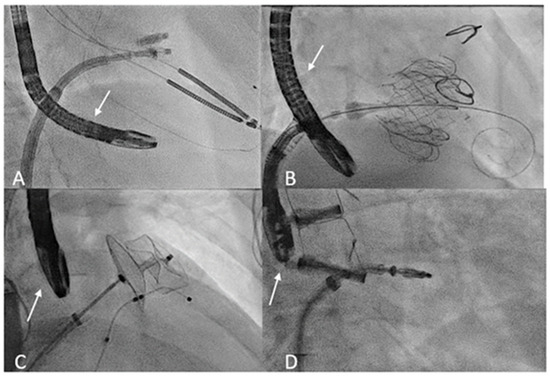

Figure 1.

Transoesophageal probe position (arrow) during transcatheter interventions. (A) The fluoroscopy shows the transgastric probe position during T-TEER. (B) Deep esophageal view used during tricuspid valve replacement. (C) Mid esophageal probe position during LAA occlusion. (D) Mid esophageal probe position used during M-TEER. T-TEER: Tricuspid Transcatheter edge-to-edge repair; LAA: left atrial appendage; M-TEER: Mitral Transcatheter edge-to-edge repair.